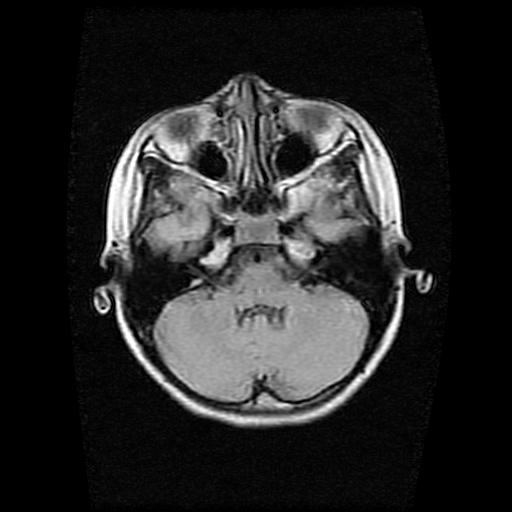

9岁女孩,三岁时诊断为癫痫,一直服丙戊酸钠,现患者一般情况良好,家长复查核磁片,看能否停药..

巨脑回

未见异常信号灶.

未发现异常信号。